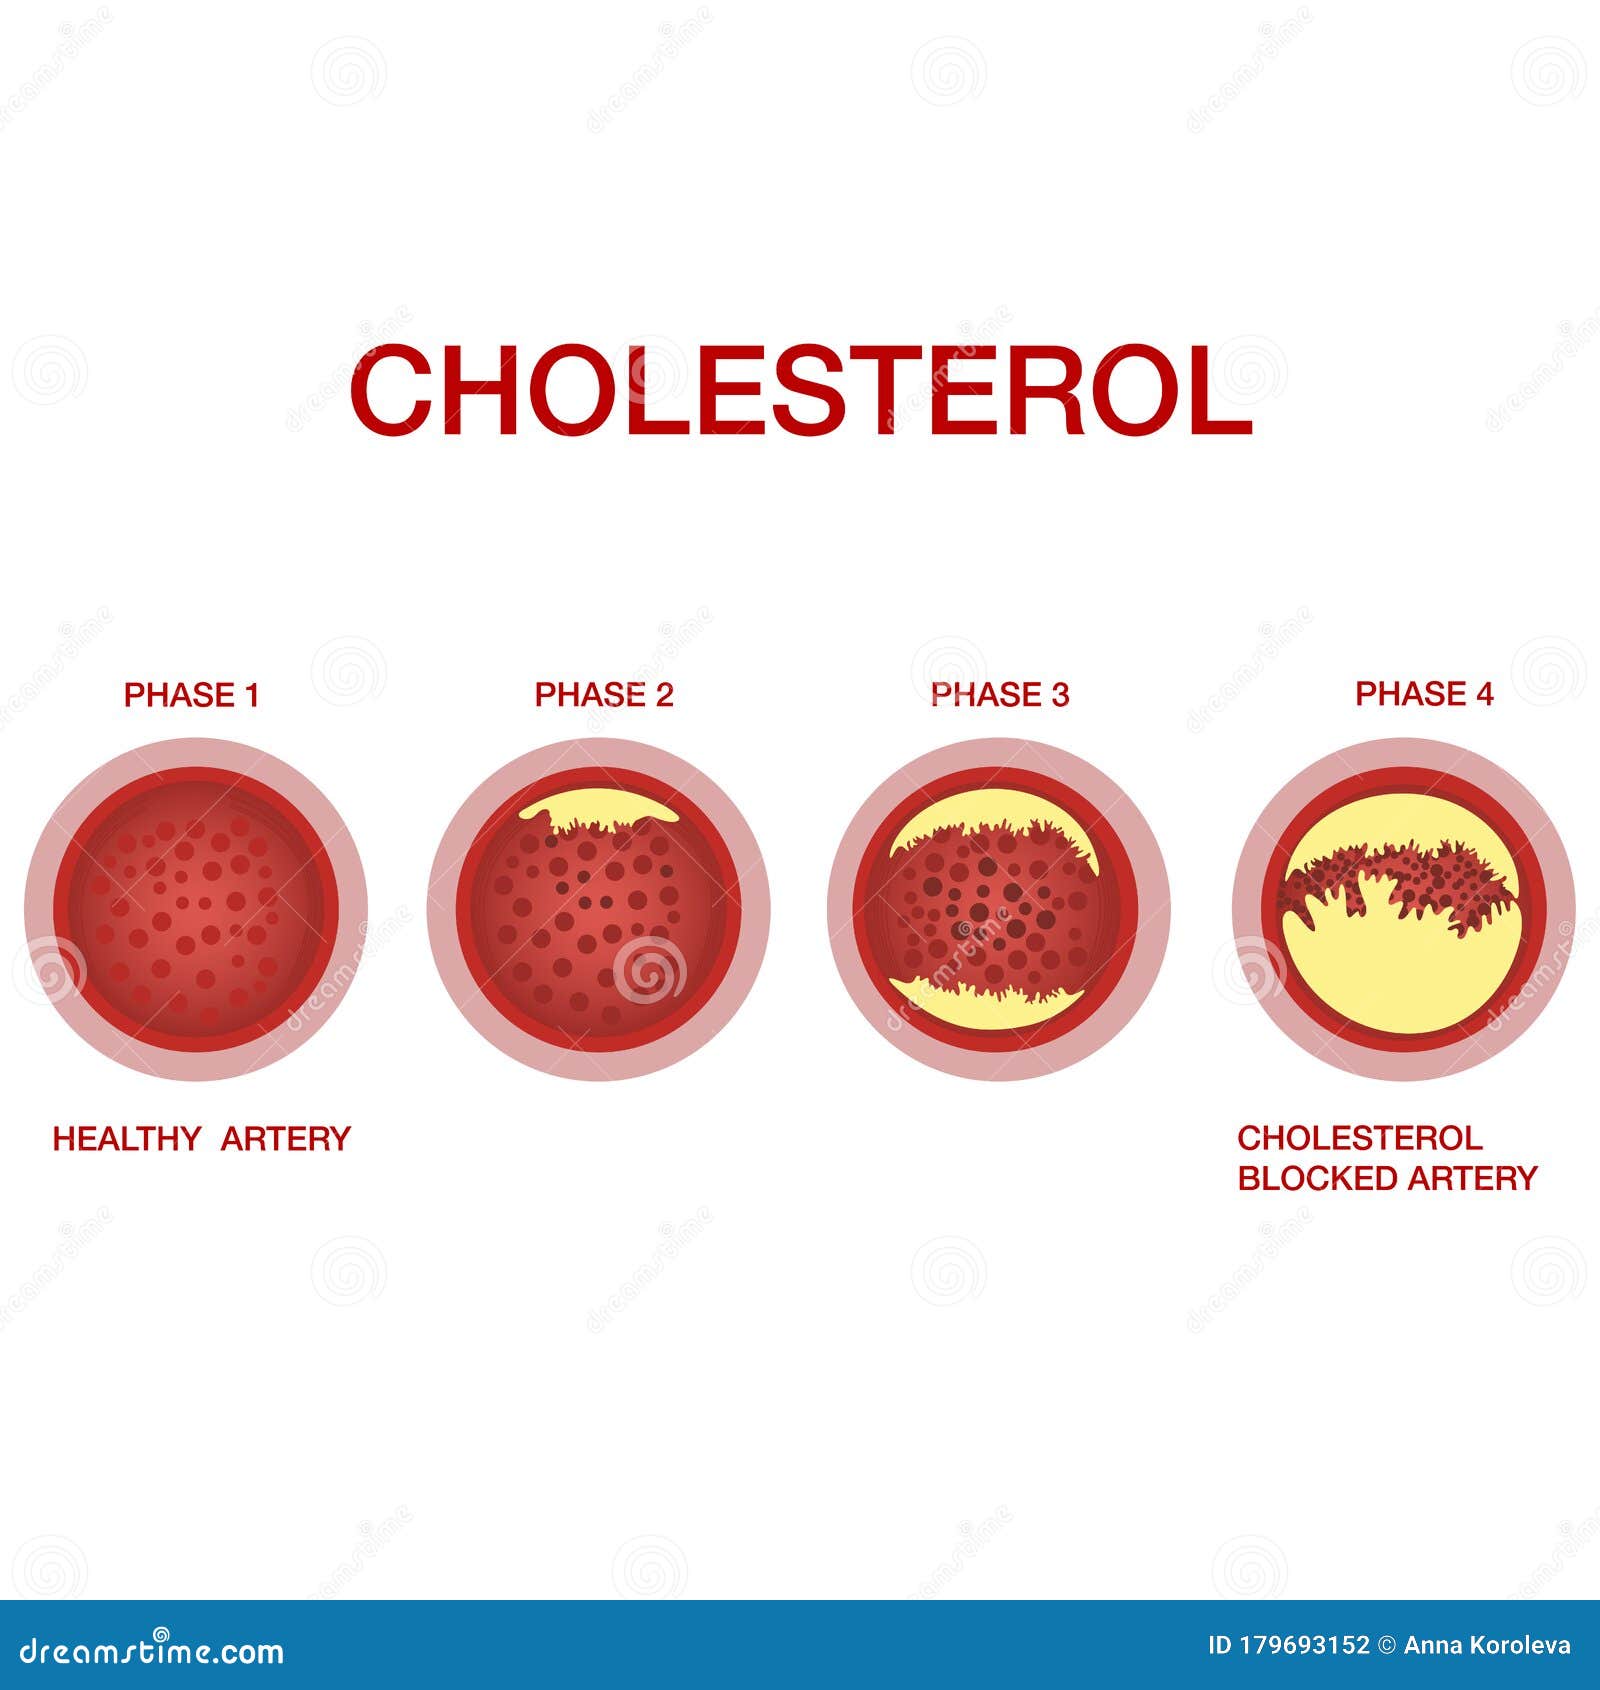

Atherosclerosis Stages: Healthy Artery, Plaque Formation, and …

Stages of atherosclerosis Stock Vector Image by ©edesignua #144301487

Atherosclerosis stages. Normal functions, endothelia disfunction …

Different stages in progression of atherosclerosis [8]. | Download …